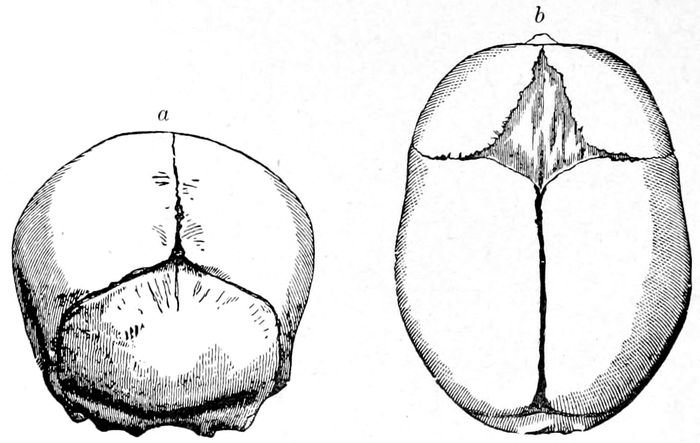

Fig. 21.—Fœtal skulls showing sutures. Note the differences between the anterior and posterior fontanelles. (Eden.)

Fig. 22 A.—Child’s head at term (from side), showing diameter. (American Text Book.)

Fig. 22 B.—The child’s head at term (from above), showing diameters and fontanelles. (American Text Book.)

46The fœtal skull at maturity (at term) is still incompletely ossified. The bones are thin and pliable and

In front, the two coronary sutures meet the frontal

and sagittal sutures to produce a kite-shaped figure,

called the large or anterior fontanelle, or the bregma.

Behind, the lambdoidal suture meets the sagittal suture

to form the small or posterior fontanelle.

The large fontanelle is made up of four bones and

four angles; the small, of three bones and three angles,

and are usually easy to differentiate. Furthermore,

the difference between these fontanelles is of great importance

in labor, since by it the observer is enabled to

determine the position of the head. In America, the

shape of the head is that of an ovoid with the long

diameter anteroposterior (Dolico-cephalic). Thus it

happens that when the head is completely flexed, the

smallest diameters are presented for delivery.